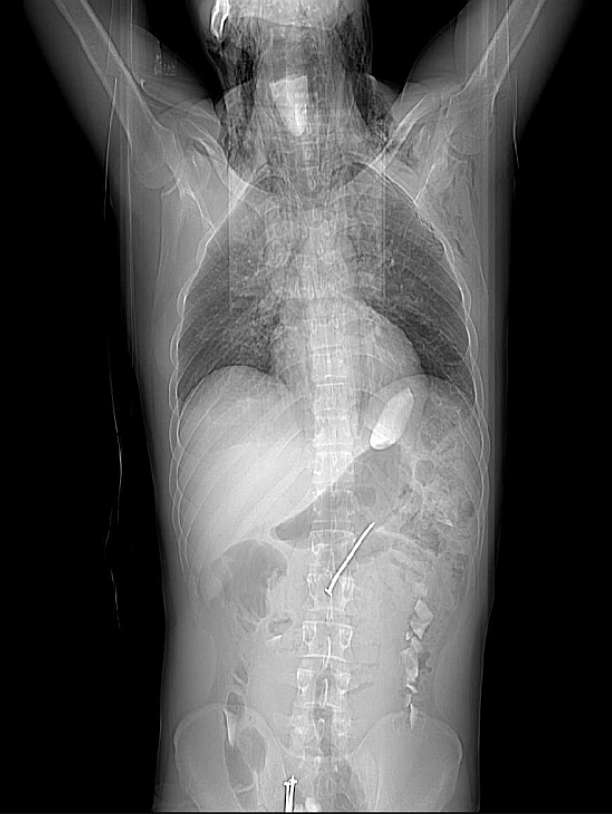

A CT examination was required to evaluate the neck and the chest. A large number of nails and stones were found along the gastrointestinal tract extending from the stomach to the rectum. A big stone was detected within the pharynx. Subcutaneous emphysema and pneumomediastinum was also seen. Patient was sent to the operating room immediately.

Plain radiography, especially lateral radiographs of the neck, may occasionally demonstrate bones or other radiopaque foreign bodies [1, 2].If we decide to administer oral CM we should always use hydrosoluble non ionic contrast agents to avoid the reaction of barium to the pleura or peritoneum.CT is also useful in evaluating oesophageal foreign body impaction. With its soft tissue and bone windowing, CT may replace the barium swallow because of its superior detection of thin, small, minimally calcified foreign bodies that are often obscured by overlying tissues. CT can also detect inflammatory changes in the adjacent structures.

CT features of oesophageal perforation include oesophageal wall thickening, perioesophageal fluid, perioesophageal air, pleural effusion, and pericardial effusion, oesophageal wall laceration, and extravasation of oral contrast material. Pleural effusions are usually bilateral. CT is ideally suited for defining the extent of extraluminal air-fluid collection and for detecting small amounts of extravasated contrast material. In addition, CT may also be useful in monitoring the clinical course of patients treated conservatively [3, 4, 5].